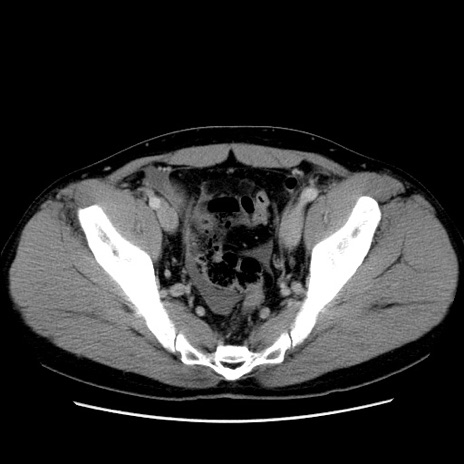

冠状断像

【症例】30歳代男性

【主訴】腹痛、嘔吐

【現病歴】昨晩から突然の腹痛あり、その後嘔吐、軟便も出現。腹痛が改善しないため救急搬送となる。2日前にしめ鯖の食事歴あり。

【身体所見】意識清明、苦悶様、BP 135/90mmHg、BT 35.7℃、腹部:平坦、やや硬、心窩部〜臍部に自発痛、圧痛あり、筋性防御+、反跳痛-

【データ】WBC 8100、CRP 0.57